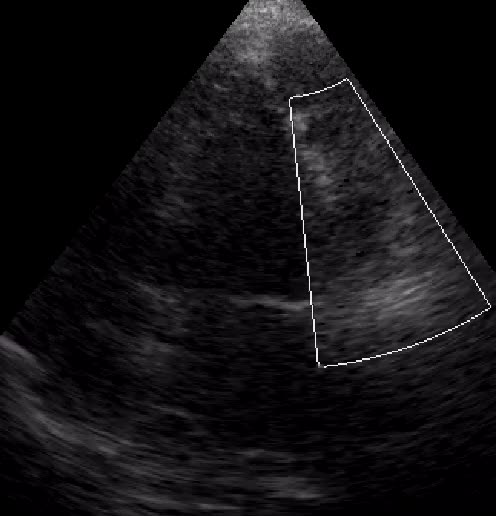

Color Doppler come va impostato

Autore:

Eleonora Zenoni